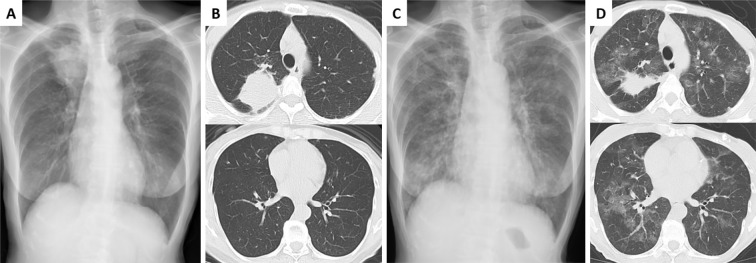

表皮生长因子受体(EGFR)酪氨酸激酶抑制剂(TKIs)对EGFR突变的非小细胞肺癌非常有效,但可能导致严重的不良事件,如间质性肺疾病(ILD)。奥西替尼诱导的ILD的治疗策略尚未很好地确定。首先考虑的是细胞毒性抗癌药物,尽管已经报道了几例成功的EGFR-TKIs再挑战。我们在此报告一名67岁的妇女,她有症状性的奥西替尼诱导ILD,她被切换到阿法替尼,后来再次使用奥西替尼和皮质类固醇。这两种治疗方法都没有导致ILD复发,这表明当其他治疗方法有限时,这些可能是可行的治疗选择。

Epidermal growth factor receptor (EGFR) tyrosine kinase inhibitors (TKIs) are highly effective against EGFR-mutant non-small-cell lung carcinoma but can cause serious adverse events, such as interstitial lung disease (ILD). Treatment strategies for osimertinib-induced ILD are not well established. Cytotoxic anticancer drugs are considered first, although several cases of successful rechallenge with EGFR-TKIs have been reported. We herein report a 67-year-old woman with symptomatic osimertinib-induced ILD who was switched to afatinib and later rechallenged with osimertinib and corticosteroids. Neither treatment resulted in ILD relapse, suggesting that these may be viable treatment options when alternative treatments are limited.